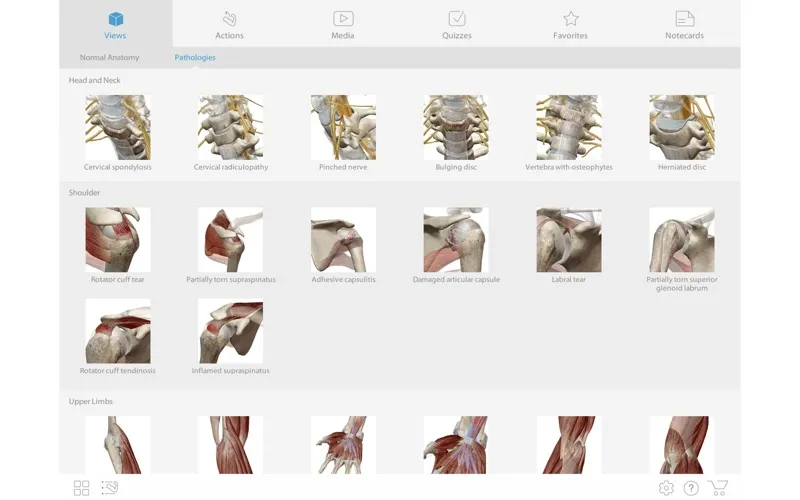

* 📚 Nghiên cứu các bệnh lý cơ xương khớp phổ biến thông qua các mô hình 3D chuyên sâu và video minh họa từ chuyên gia 🎬.

* ✅ Kiểm tra kiến thức với các bài quiz tương tác 💯 và lưu lại những kiến thức quan trọng bằng Notecards tiện lợi 📌.

Người dùng Muscle Premium sẽ có cơ hội được tương tác trực tiếp với mô hình dây chẳng, sợi cơ, xương,… Bên cạnh đó, ứng dụng cung cấp thông tin về các chấn thương liên quan đến cơ xương khớp.